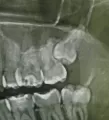

Сделав рентген, врач сказал, что требуется вмешательство стоматолога-хирурга. Так как 8-й зуб уперся в 7-й и именно это является причиной боли. С этим я с ним согласен. Но он сказал, что рано или поздно придется делать операцию и удалять 8-й зуб, так как он сам не прорастет. И главное он говорил, так как будто нет шансов, что зуб сам сможет прорасти.

Действительно, Ваш зуб самостоятельно прорезаться не может, потому что он "лежит" по направлению к 7-му зубу, самостоятельно он может двигаться только в сторону 7-го.

Предстоит операция, но это операция не в широком смысле этого слова.

Под местной анестезией врач стоматолог-хирург вскроет участок костной ткани (создаст своеобразное окошко в области 8-го зуба) и достанет его.